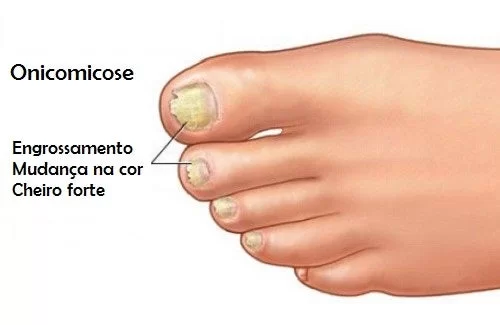

E o que causa essa bagunça toda? Pode ser uma micose traiçoeira, que se alimenta da queratina da sua unha, deixando ela grossa, amarelada e deformada. Ou então, um trauma direto, tipo aquele tombo feio ou até um sapato que aperta demais e fica ali, incomodando dia após dia.

A verdade é que muita gente ignora os primeiros sinais, acha que é só um probleminha estético. Mas pode confessar: quando a unha começa a ficar amarelada, grossa, e com aquele espaço estranho por baixo, bate uma preocupação. É fundamental entender o que está rolando para não transformar um pequeno incômodo em um problemão de saúde.

Micose (onicomicose) é uma causa comum de unha oca, alimentando-se da queratina e alterando cor e textura.

A unha amarelada, grossa e deformada é um sinal clássico de micose de unha.

Micoses nas unhas, ou onicomicose, podem causar desconforto e afetar a estética.